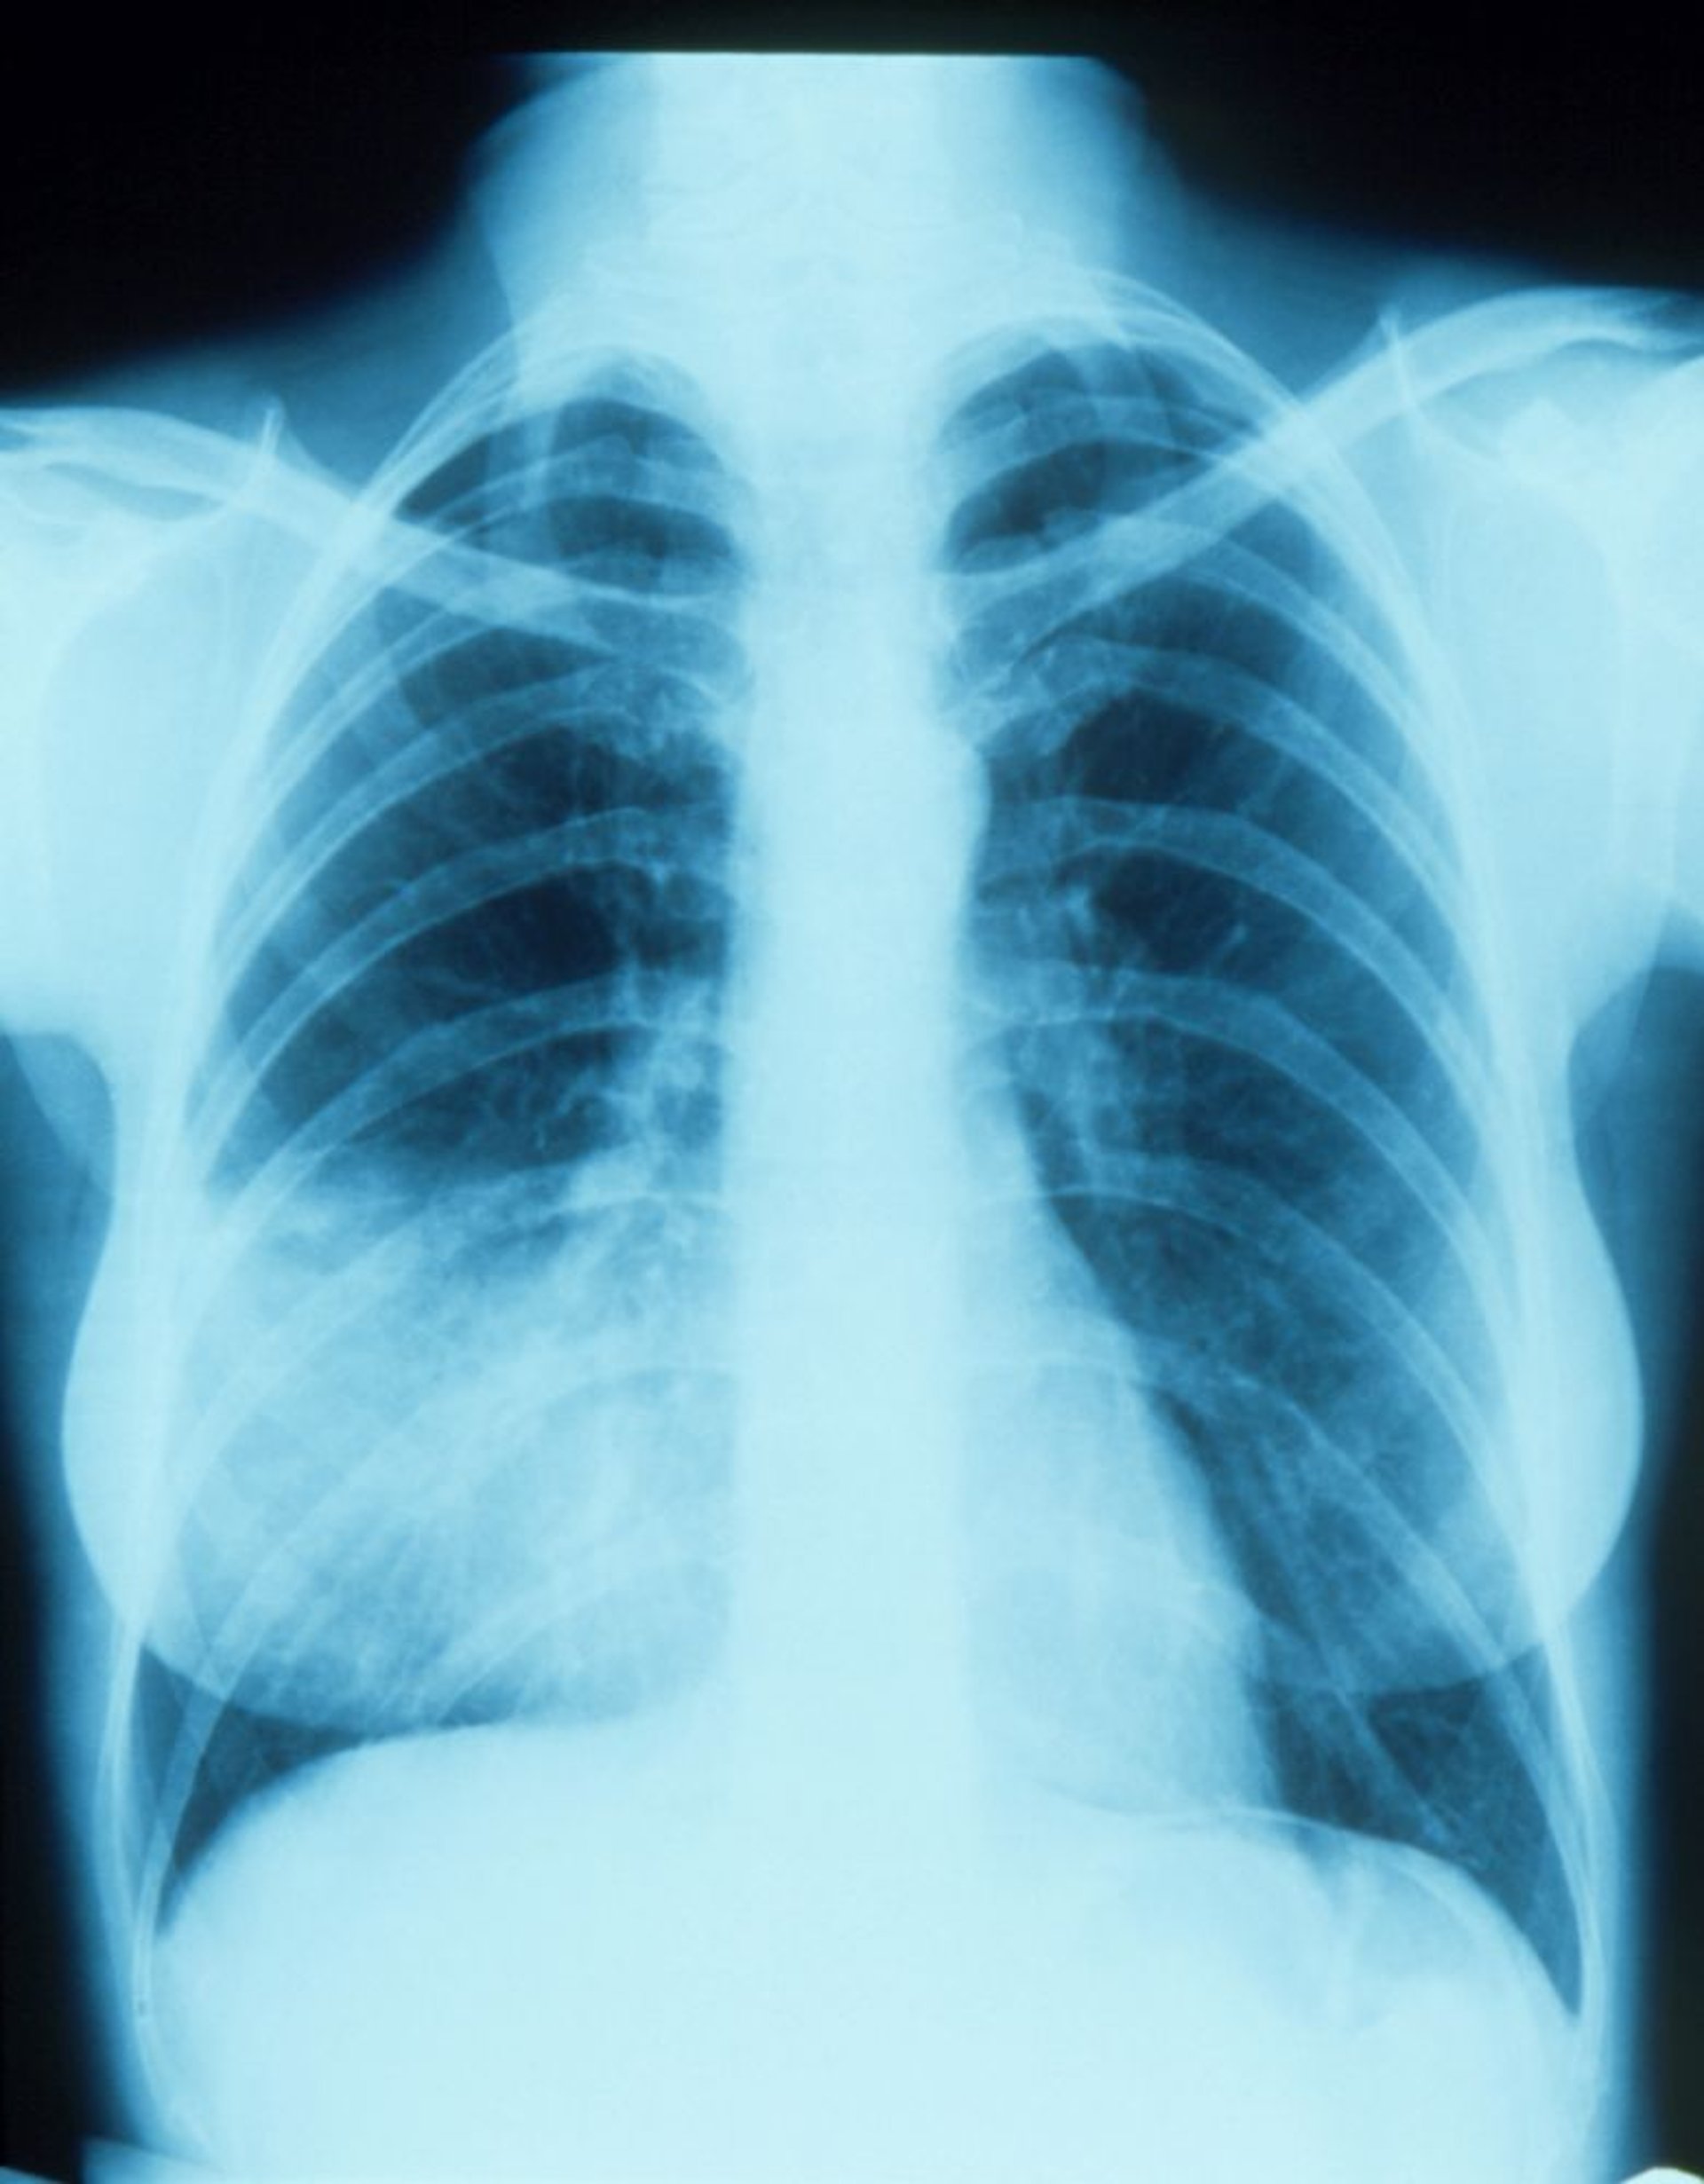

Pneumonie du lobe moyen droit avec signe de la silhouette

Cette radiographie pulmonaire montre un infiltrat qui semble se fondre avec le bord droit du cœur (signe de la silhouette). Le signe de la silhouette est dû au positionnement contigu des 2 structures de même densité; la partie du poumon contiguë au bord droit du cœur est le lobe moyen droit, c'est-à-dire la partie infiltrée et la pneumonie.